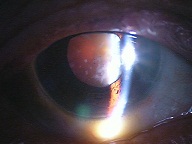

今日いらした24歳女性の症例です。

強い充血を認めます。写真の右側は、はやり目に特徴的な後遺症で、黒目(角膜)が濁っている写真です。もう少し分かりやすい、ヒドイ症例の写真を出したいのですが、ヒドイ症例は第一診察室には入らないようにしていただいたり、写真をとるなどの、余分な時間を少しでも省いて診療を行い、院内感染を予防する必要があり、なかなか難しいのです。